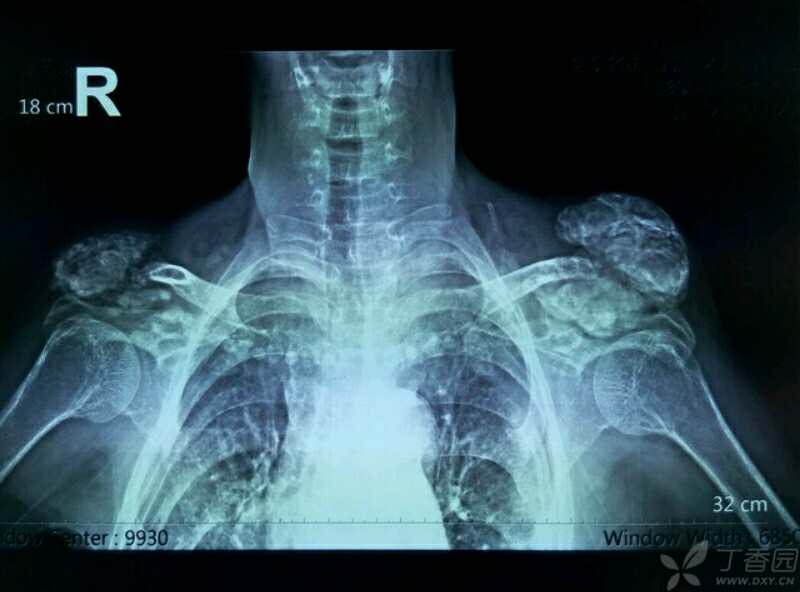

(fop患者的x光片,异位骨化影响整个骨骼系统的形态,除局部的变形之外

图片尺寸519x681